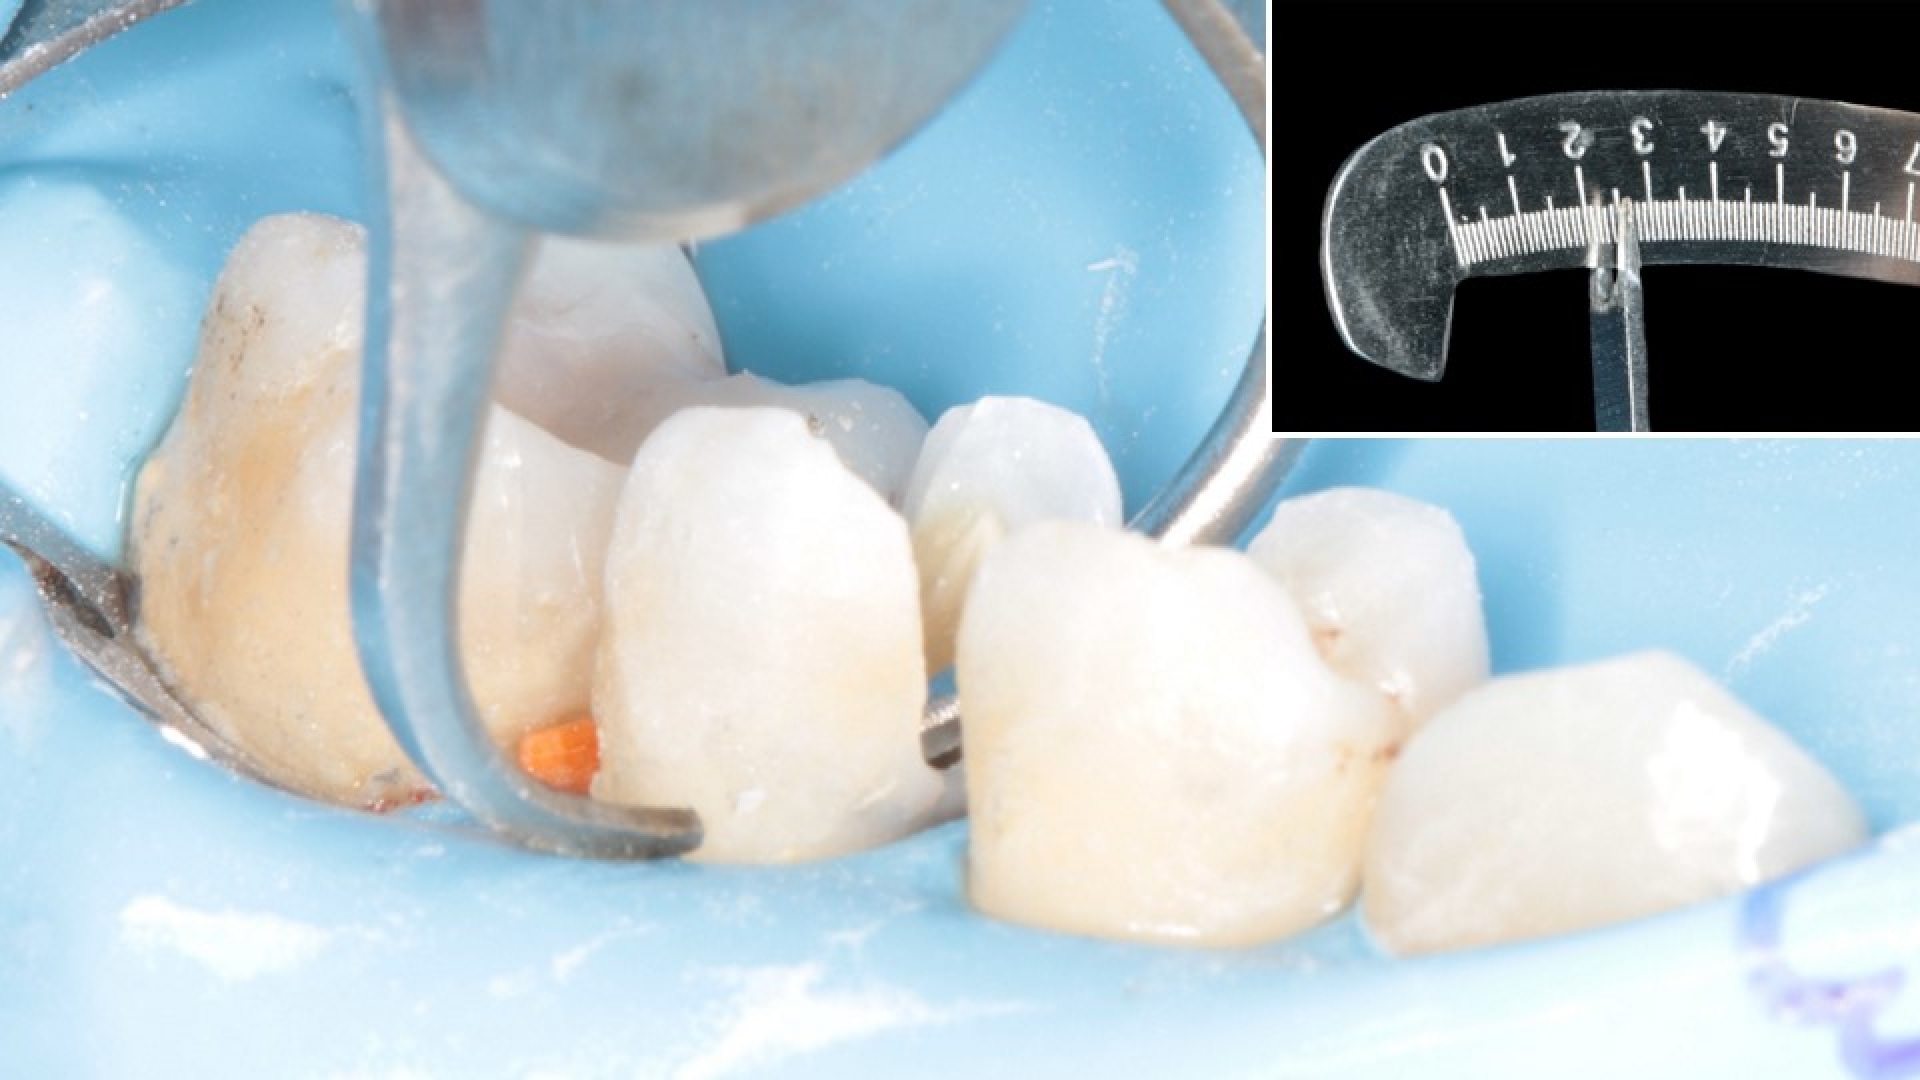

Both Amalgam restorations were completely removed establishing a proper enamel margin while maintaining pulp vitality. The cavity was excessively large in the second premolar compromising both marginal ridges.

Further analysis of the situation was needed to determine whether to go for a direct or indirect restoration of the second premolar. A caliber was used to measure the base thickness of the buccal and lingual walls.

Stage 4. Restoration Choice

Both walls were found to be greater than 2 mm in thickness. Therefore, a direct restoration using composite was chosen